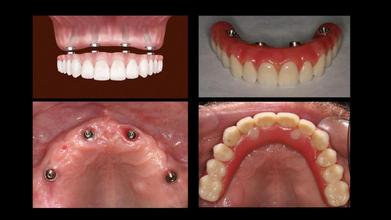

3、植體固定式假牙——All on 4全口重建/all-on-6全口重建

All on 4/all-on-6全口重建係針對骨骼嚴重萎縮、而且需要快速恢復牙齒的人而設計嘅。同傳統植牙相比,最明顯嘅優勢就係速度,若口腔條件允許,最快可以在一日之內完成全口植牙與假牙,唔需要好似傳統植牙一次等待3~6個月以上嘅治療週期。

All on 4/all-on-6全口重建只需要四顆或者六顆植牙,可以大幅縮短手術時間、節省植體費用。

無論是固定式假牙All on 4、All on 6,使用單顎4支/6支植體做為人工牙根,固定於牙床上,藉由拱橋力學設計原理,平均分散植體力量去支撐整排假牙。因此,固定式植牙最接近自然牙的假牙形式,唔單單穩定性高、咬合力佳,亦沒有活動式假牙的異物感。